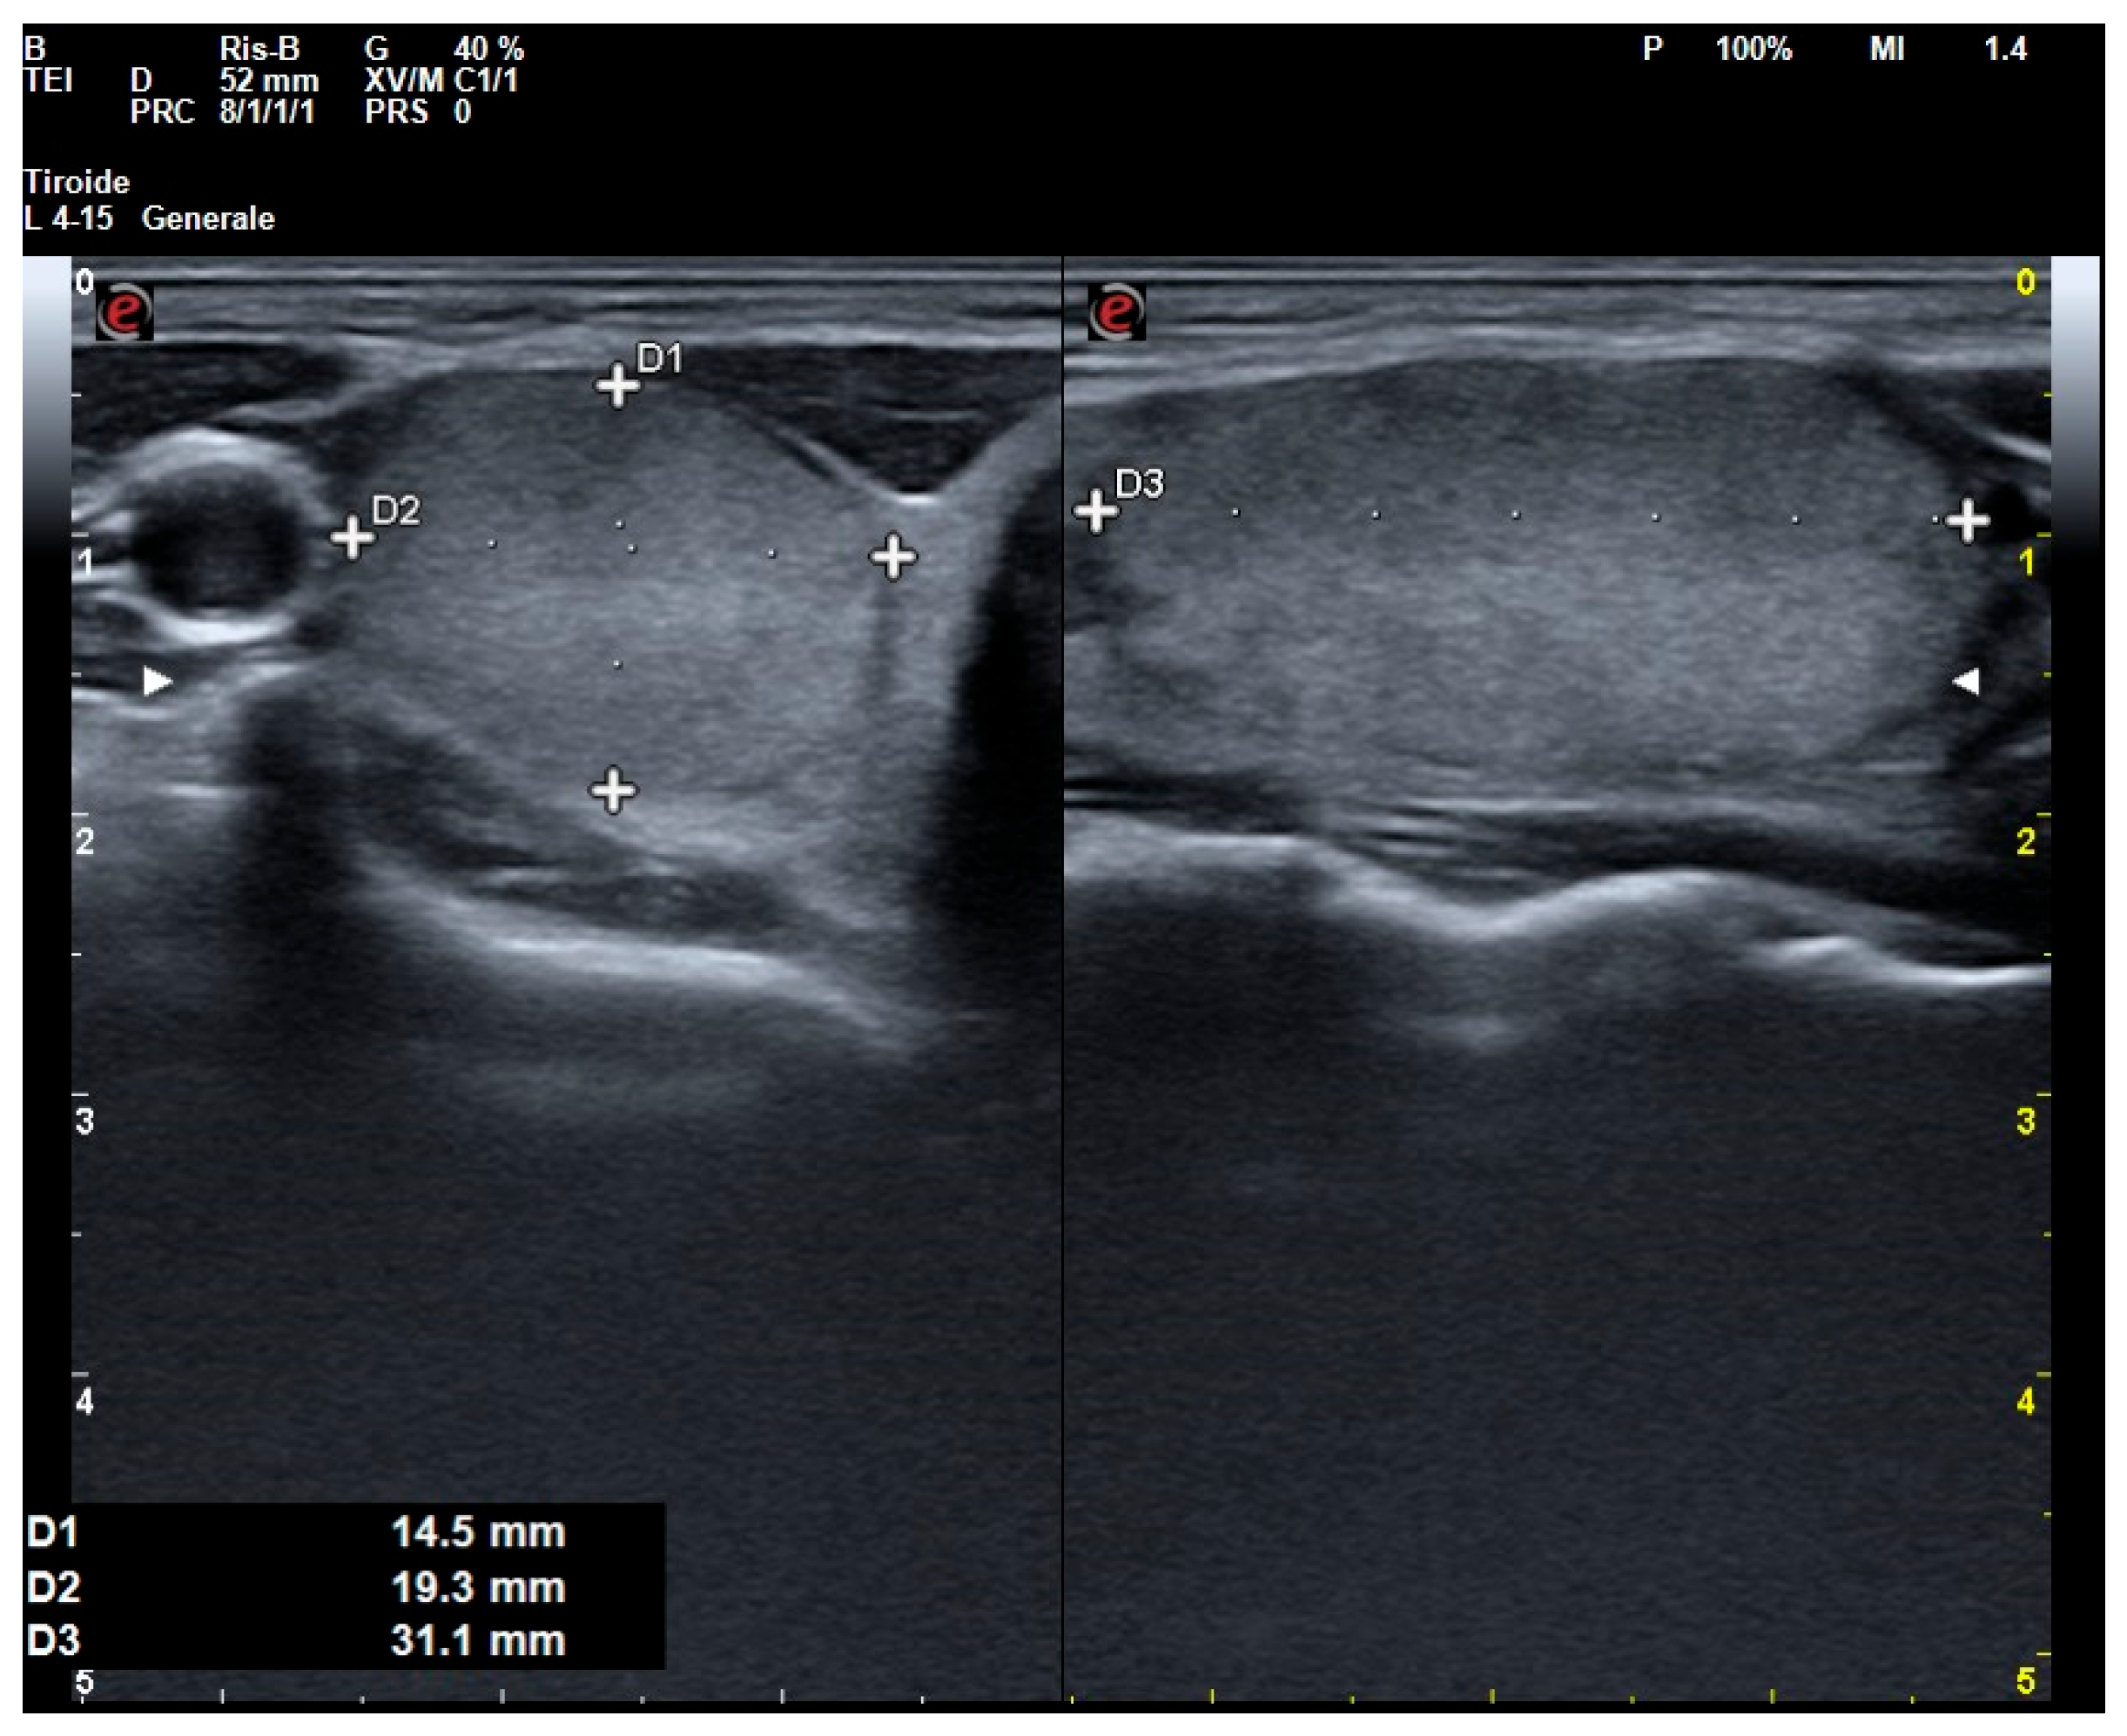

| Nodule’s US data | |

| Maximum ITN diameter, mm (IQR) | 15.0 (10.0–20.0) |

| ACR TI-RADS (1; 2; 3; 4; 5), % | 0.0; 1.1; 26.0; 61.0; 11.9 |

| Composition (cystic or almost completely cystic, spongiform, mixed cystic and solid, or solid or almost completely solid), % | 0.0; 0.0; 4.0; 96.0 |

| Echogenicity (anechoic, hyperechoic or isoechoic, hypoechoic, or very hypoechoic), % | 0.0; 35.0; 58.8; 6.2 |

| Shape (wider than tall or taller than wide), % | 94.9; 5.1 |

| Margin (smooth, ill-defined, lobulated or irregular, or extra-thyroidal extension), % | 93.2; 0.0; 6.8; 0.0 |

| Echogenic foci (none or large comet-tail artifacts, macrocalcifications, peripheral rim calcifications, or punctate echogenic foci), % | 83.1; 11.3; 4.0; 1.6 |